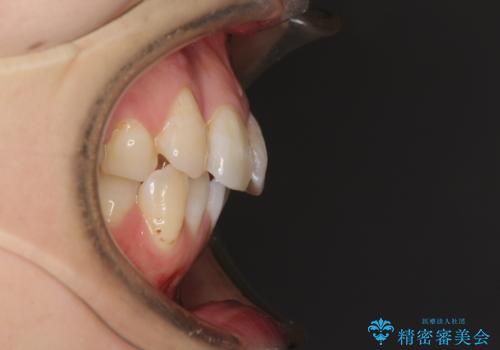

右上前から2番目の歯が内側に転位しているため、上顎の正中は右にずれていました。

右上4番目の歯を抜歯し、上顎裏側に補助装置を装着して左の歯列全体を後方に移動させながら、正中を合わせるようにして行くこととしました。